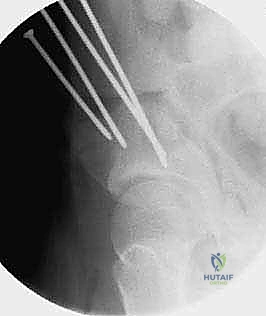

* التخطيط الجراحي الرقمي: يقوم الدكتور هطيف بدراسة الأشعة المقطعية بدقة وتحديد زوايا القطع وحجم البراغي المطلوبة لكل مريض بشكل فردي (Personalized Medicine).

2. سلسلة قطع العظام (The 5 Osteotomies)

يكمن سر نجاح جراحة PAO في إجراء خمسة قطوع عظمية منفصلة حول الحُق، لتحريره بالكامل عن باقي الحوض، مع ترك العمود الخلفي سليماً كدعامة أساسية.

تتميز جراحة PAO عن غيرها من جراحات قطع عظم الحوض القديمة (مثل قطع العظم الثلاثي لـ Steel أو Tonnis) من خلال ميزة ميكانيكية حيوية حاسمة: الحفاظ الدقيق على سلامة العمود الخلفي للحوض (Posterior Column). هذا التمييز التشريحي يقلل من عدم استقرار حلقة الحوض، يسمح للمريض بالحركة المبكرة، ويتيح للجراح إعادة توجيه متعدد المستويات لقطعة الحُق بشكل أكثر قوة ودقة. يتم تحقيق ذلك من خلال تسلسل دقيق للغاية من خمس عمليات قطع عظم (Osteotomies)، كل منها مصمم لتحرير الحُق مع الحفاظ على إمداده الدموي الحيوي.